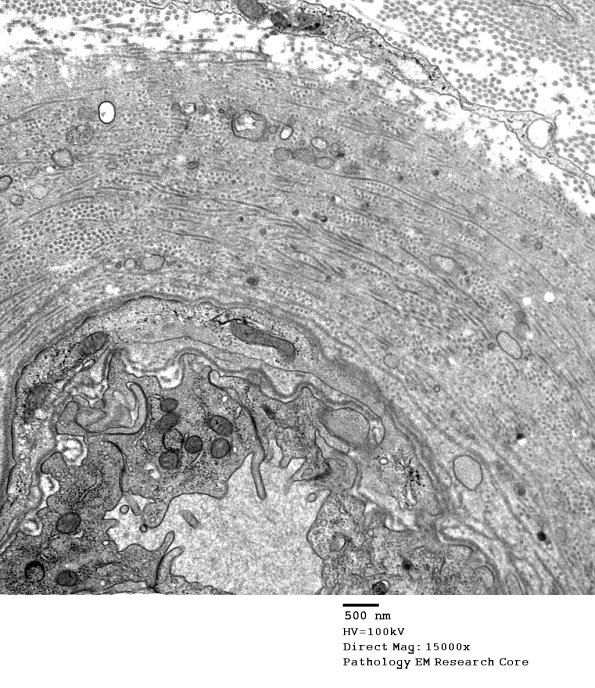

Washington University Experience | VASCULAR | Hypoxia-Ischemia, fetal-neonatal | White Matter | 1B2 Vasculopathy (Case 1) EM018 - Copy

1B2 Vasculopathy (Case 1) EM018 - Copy